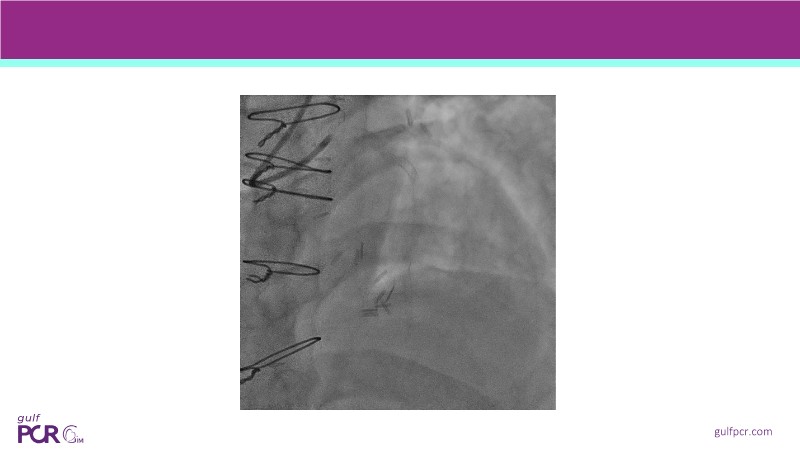

Calcified coronary lesions are a major challenge in PCI. This PCRGulf-GIM 2025 session showcases a complex case with intravascular imaging, highlighting how IVUS 123 guides each step.

From planning the procedure and understanding calcium distribution, to lesion preparation with modern modification tools, and post-PCI assessment to confirm stent expansion and detect complications, this session demonstrates practical, imaging-driven strategies.

Learn how careful preparation and modern techniques improve outcomes in treating severe calcium, calcified nodules, and in-stent restenosis.